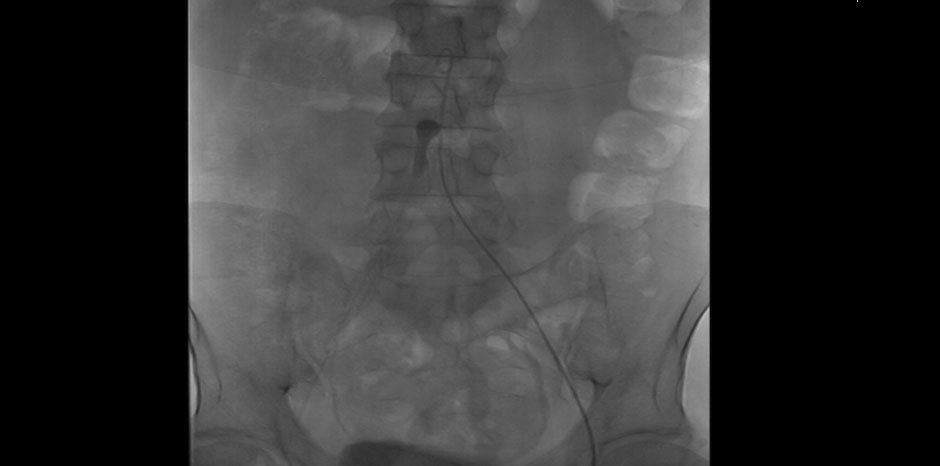

• EMBOLECTOMY BEING DONE

• BALLOONING OF STENT

RIGHT GROIN EMBOLECTOMY sos RIGHT ILIAC STENTING